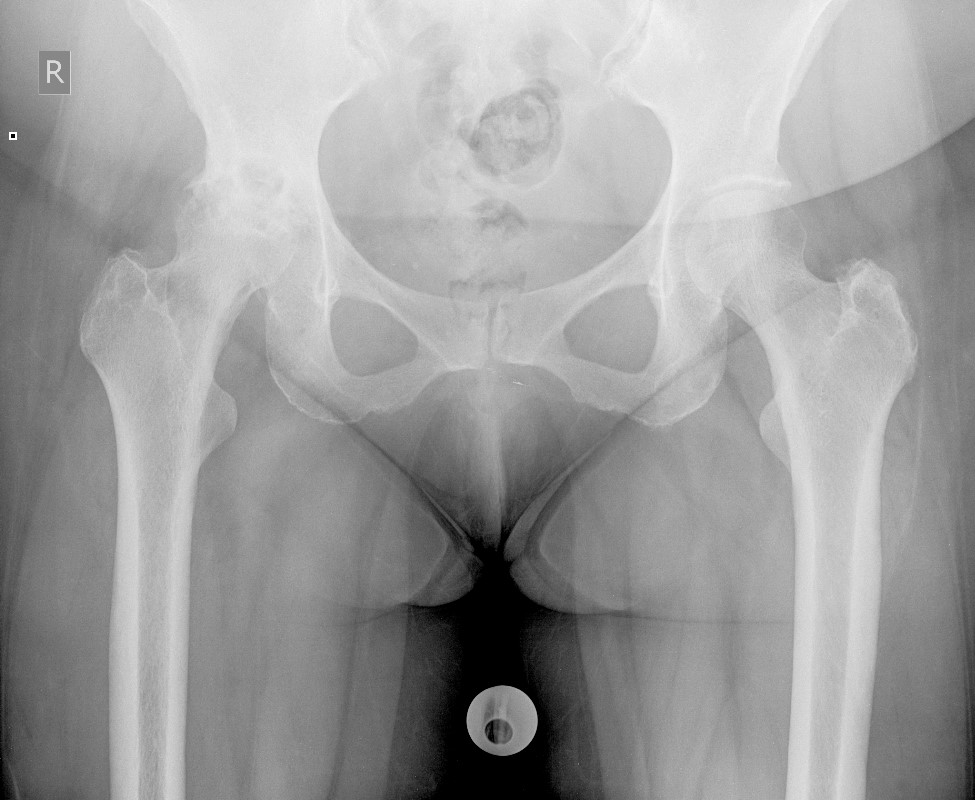

67 yo female with severe hip pain and limp

Plain film radiographs were taken.

What are your findings?